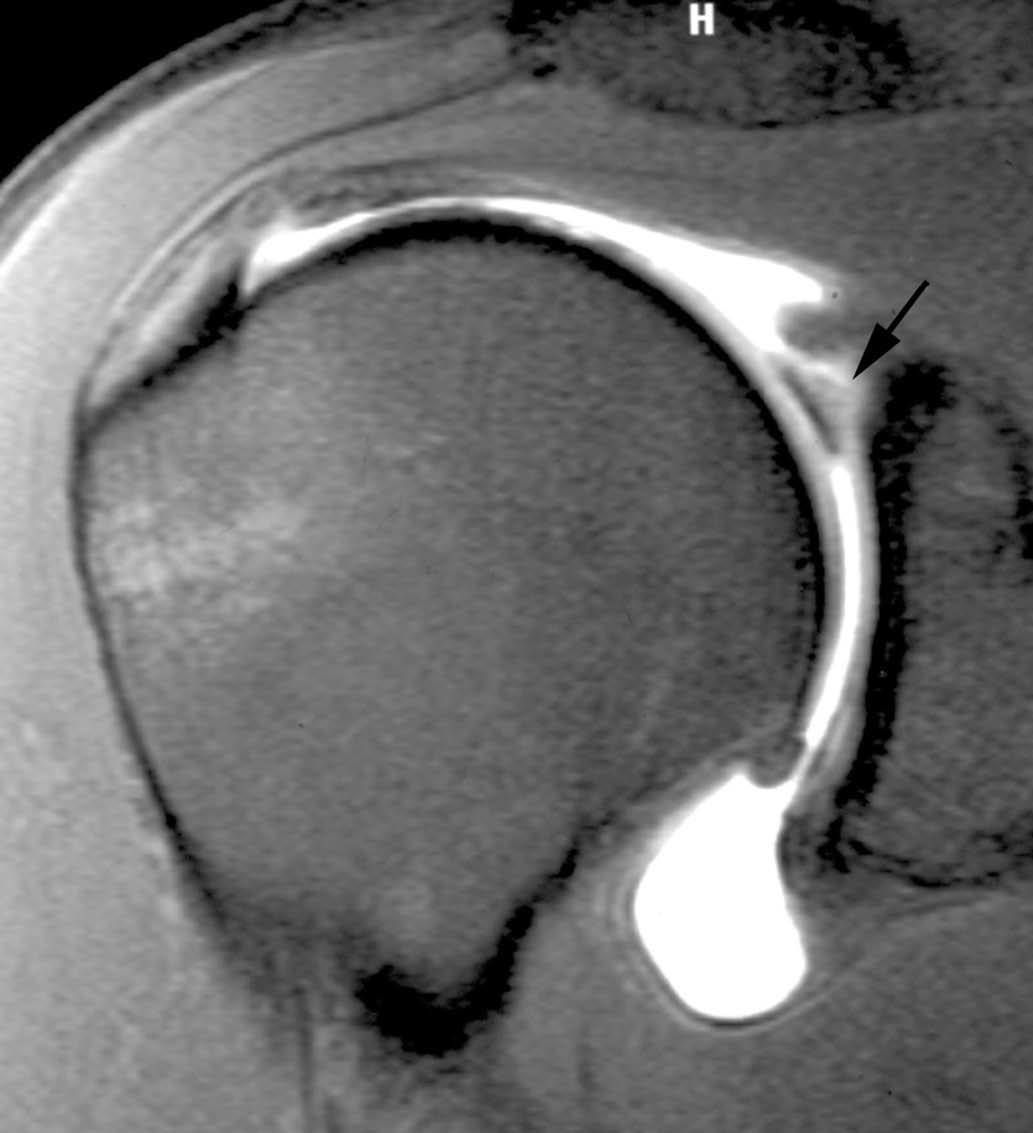

Esta lesión se produce a consecuencia de una tracción repetitiva de la unión cápsulo-perióstica posterior, produciéndose una osificación semejante a un espolón óseo (fig. 15).

Fig. 15.--Lesión de Bennett. Tomografía axial computarizada (TAC) axial (A) y resonancia magnética (RM) T1 axial (B) que revelan la presencia de un «espolón» óseo adyacente al borde glenoideo posterior (flechas en A y B). Nótese la ausencia de una lesión del labio glenoideo posterior en B.